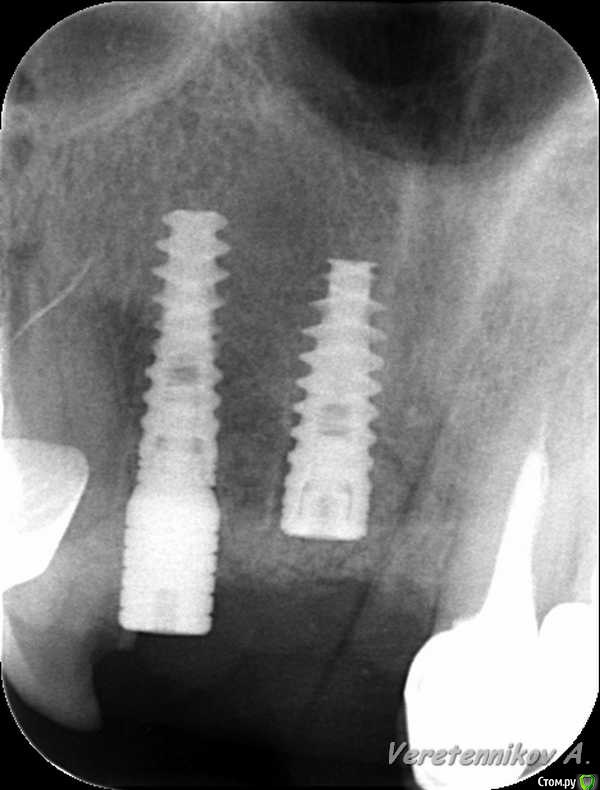

an_ver Опубликовано 26 марта, 2015 Поделиться Опубликовано 26 марта, 2015 (изменено) 11,12..11 трещина корня,вест.часть,12 рыхло все..сгнило.Убрал,кюретаж,11 вест. стенки нет на 2/3.Установил 11-4,2*13;12-3,75*13 мм..все Альфа.Мп3,мембрана эволюшн.11 заглушил,12-временный абатмент,коронка.Шил викрил 4,0. Фсе...пинайте Изменено 26 марта, 2015 пользователем an_ver 7 Ссылка на комментарий

колесников Опубликовано 26 марта, 2015 Поделиться Опубликовано 26 марта, 2015 Дело вкуса ,но я бы взял 11,5мм и 11ый поглубже поставил. Был неприятный опыт с длинными имплантами во фронте. Толи из-за анатомии ,то-ли из-за плеча, но получалась окончатая резорбция в области алекса импланта. Ссылка на комментарий

an_ver Опубликовано 27 марта, 2015 Автор Поделиться Опубликовано 27 марта, 2015 Дело вкуса ,но я бы взял 11,5мм и 11ый поглубже поставил. Был неприятный опыт с длинными имплантами во фронте. Толи из-за анатомии ,то-ли из-за плеча, но получалась окончатая резорбция в области алекса импланта.У меня такая мысль была...но стабилизация блин))...тут и так ниже ЦЭС на 3 мм Ссылка на комментарий